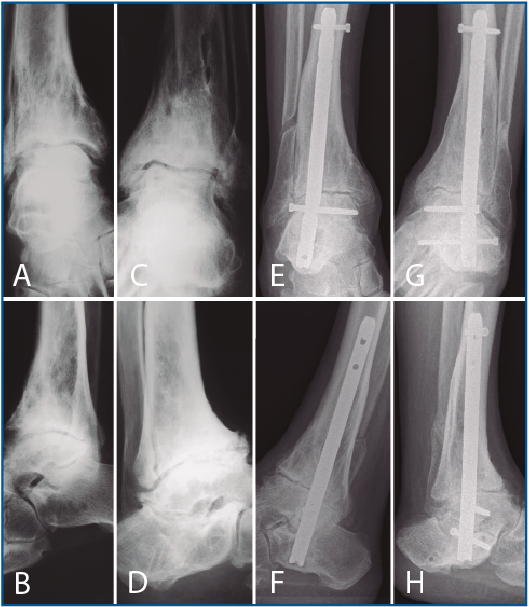

La segunda artrodesis se llevó a cabo durante el año siguiente a la primera intervención. La artrodesis fue tibioastragalina bilateral en 2 pacientes y tibiotalocalcánea (TTC) bilateral en el paciente restante. La estabilización ósea se realizó en un caso con 2 tornillos canulados Acutrak Plus® (Acumed, Hillsboro, EE. UU.) cruzados en ambos tobillos (Figura 1), en otro caso con clavo endomedular retrógrado T2 12 × 200 mm (Stryker, Schönkirchen, Alemania) en ambos tobillos (Figura 2) y en el último caso se utilizaron tornillos canulados Acutrak Plus® cruzados en el tobillo izquierdo y la técnica Putti en el tobillo derecho (Figura 3). La fijación de la artrodesis se realizó con el pie en plantígrado.

Figura 2. Caso 2. Varón de 58 años con artrosis bilateral de tobillo postraumatismo. Radiografía anteroposterior (A) y lateral (B) de tobillo derecho e izquierdo (C-D) preoperatoria. Radiografía anteroposterior y lateral de tobillo que muestra artrodesis tibiocalcánea de tobillo mediante clavo endomedular derecho (E-F) e izquierdo (G-H) a los 3 años de la última intervención (tobillo derecho). En las radiografías (E-H) muestra una consolidación parcial de la artrodesis sobre todo en la parte anterior de la articulación tibioastragalina que no se trató al ser asintomática.